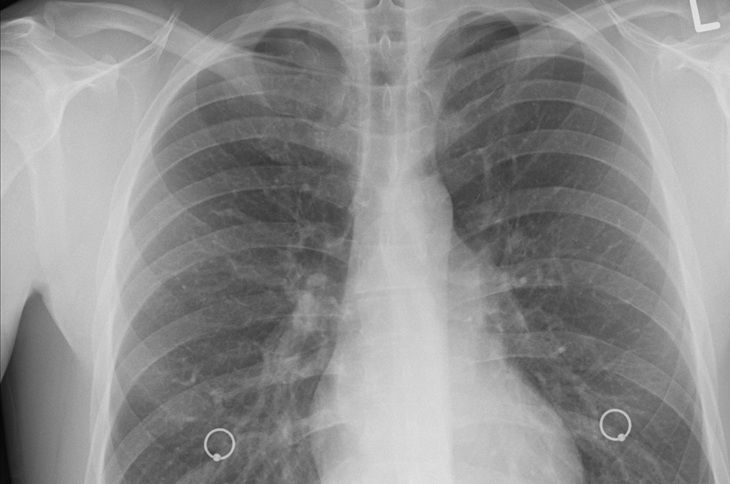

Рак легких (нужна КТ).

Пневмонию (диагностирует рентген).